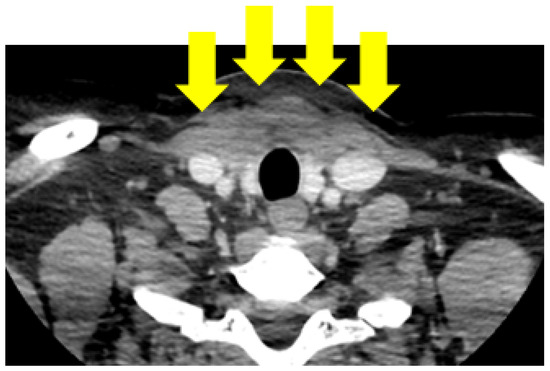

4.1.1. First Admission

4.1.4. Redo Thyroidectomy